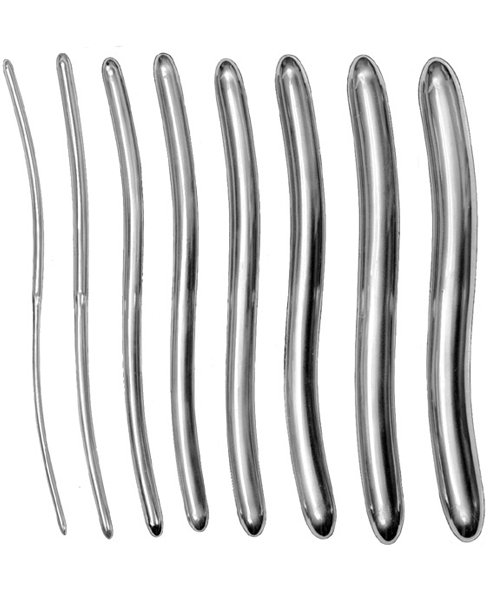

- Surgical Instruments, Urology

Gall Duct Dilator

- Size : 21 CM - 8 1/4"

- Read more

-

- Surgical Instruments, Urology

Gall Duct Dilator

- Size : 21 CM - 8 1/4"

- Read more

-

- Surgical Instruments, Urology

Gall Duct Dilator

- Size : 32 CM - 12 1/2"

- Read more

-

- Surgical Instruments, Urology

Gall Duct Dilator

- Size : 32 CM - 12 1/2"

- Read more

-

- Surgical Instruments, Urology

Gall Duct Dilator

- Size : 32 CM - 12 1/2"

- Read more

-

- Surgical Instruments, Urology

Gall Duct Dilator

- Size : 32 CM - 12 1/2"

- Read more

-

- Surgical Instruments, Urology

Gall Duct Dilator

- Size : 32 CM - 12 1/2"

- Read more

-

- Surgical Instruments, Urology

Gall Duct Dilator

- Size : 32 CM - 12 1/2"

- Read more

-

- Surgical Instruments, Urology

Gall Duct Dilator

- Size : 32 CM - 12 1/2"

- Read more

-

- Surgical Instruments, Urology

Gall Duct Dilator

- Size : 32 CM - 12 1/2"

- Read more

-

- Surgical Instruments, Urology

Gall Duct Dilator

- Size : 32 CM - 12 1/2"

- Read more

-

- Surgical Instruments, Urology

Gall Duct Dilator

- Size : 32 CM - 12 1/2"

- Read more

-

- Surgical Instruments, Urology

Gall Duct Dilator

- Size : 32 CM - 12 1/2"

- Read more